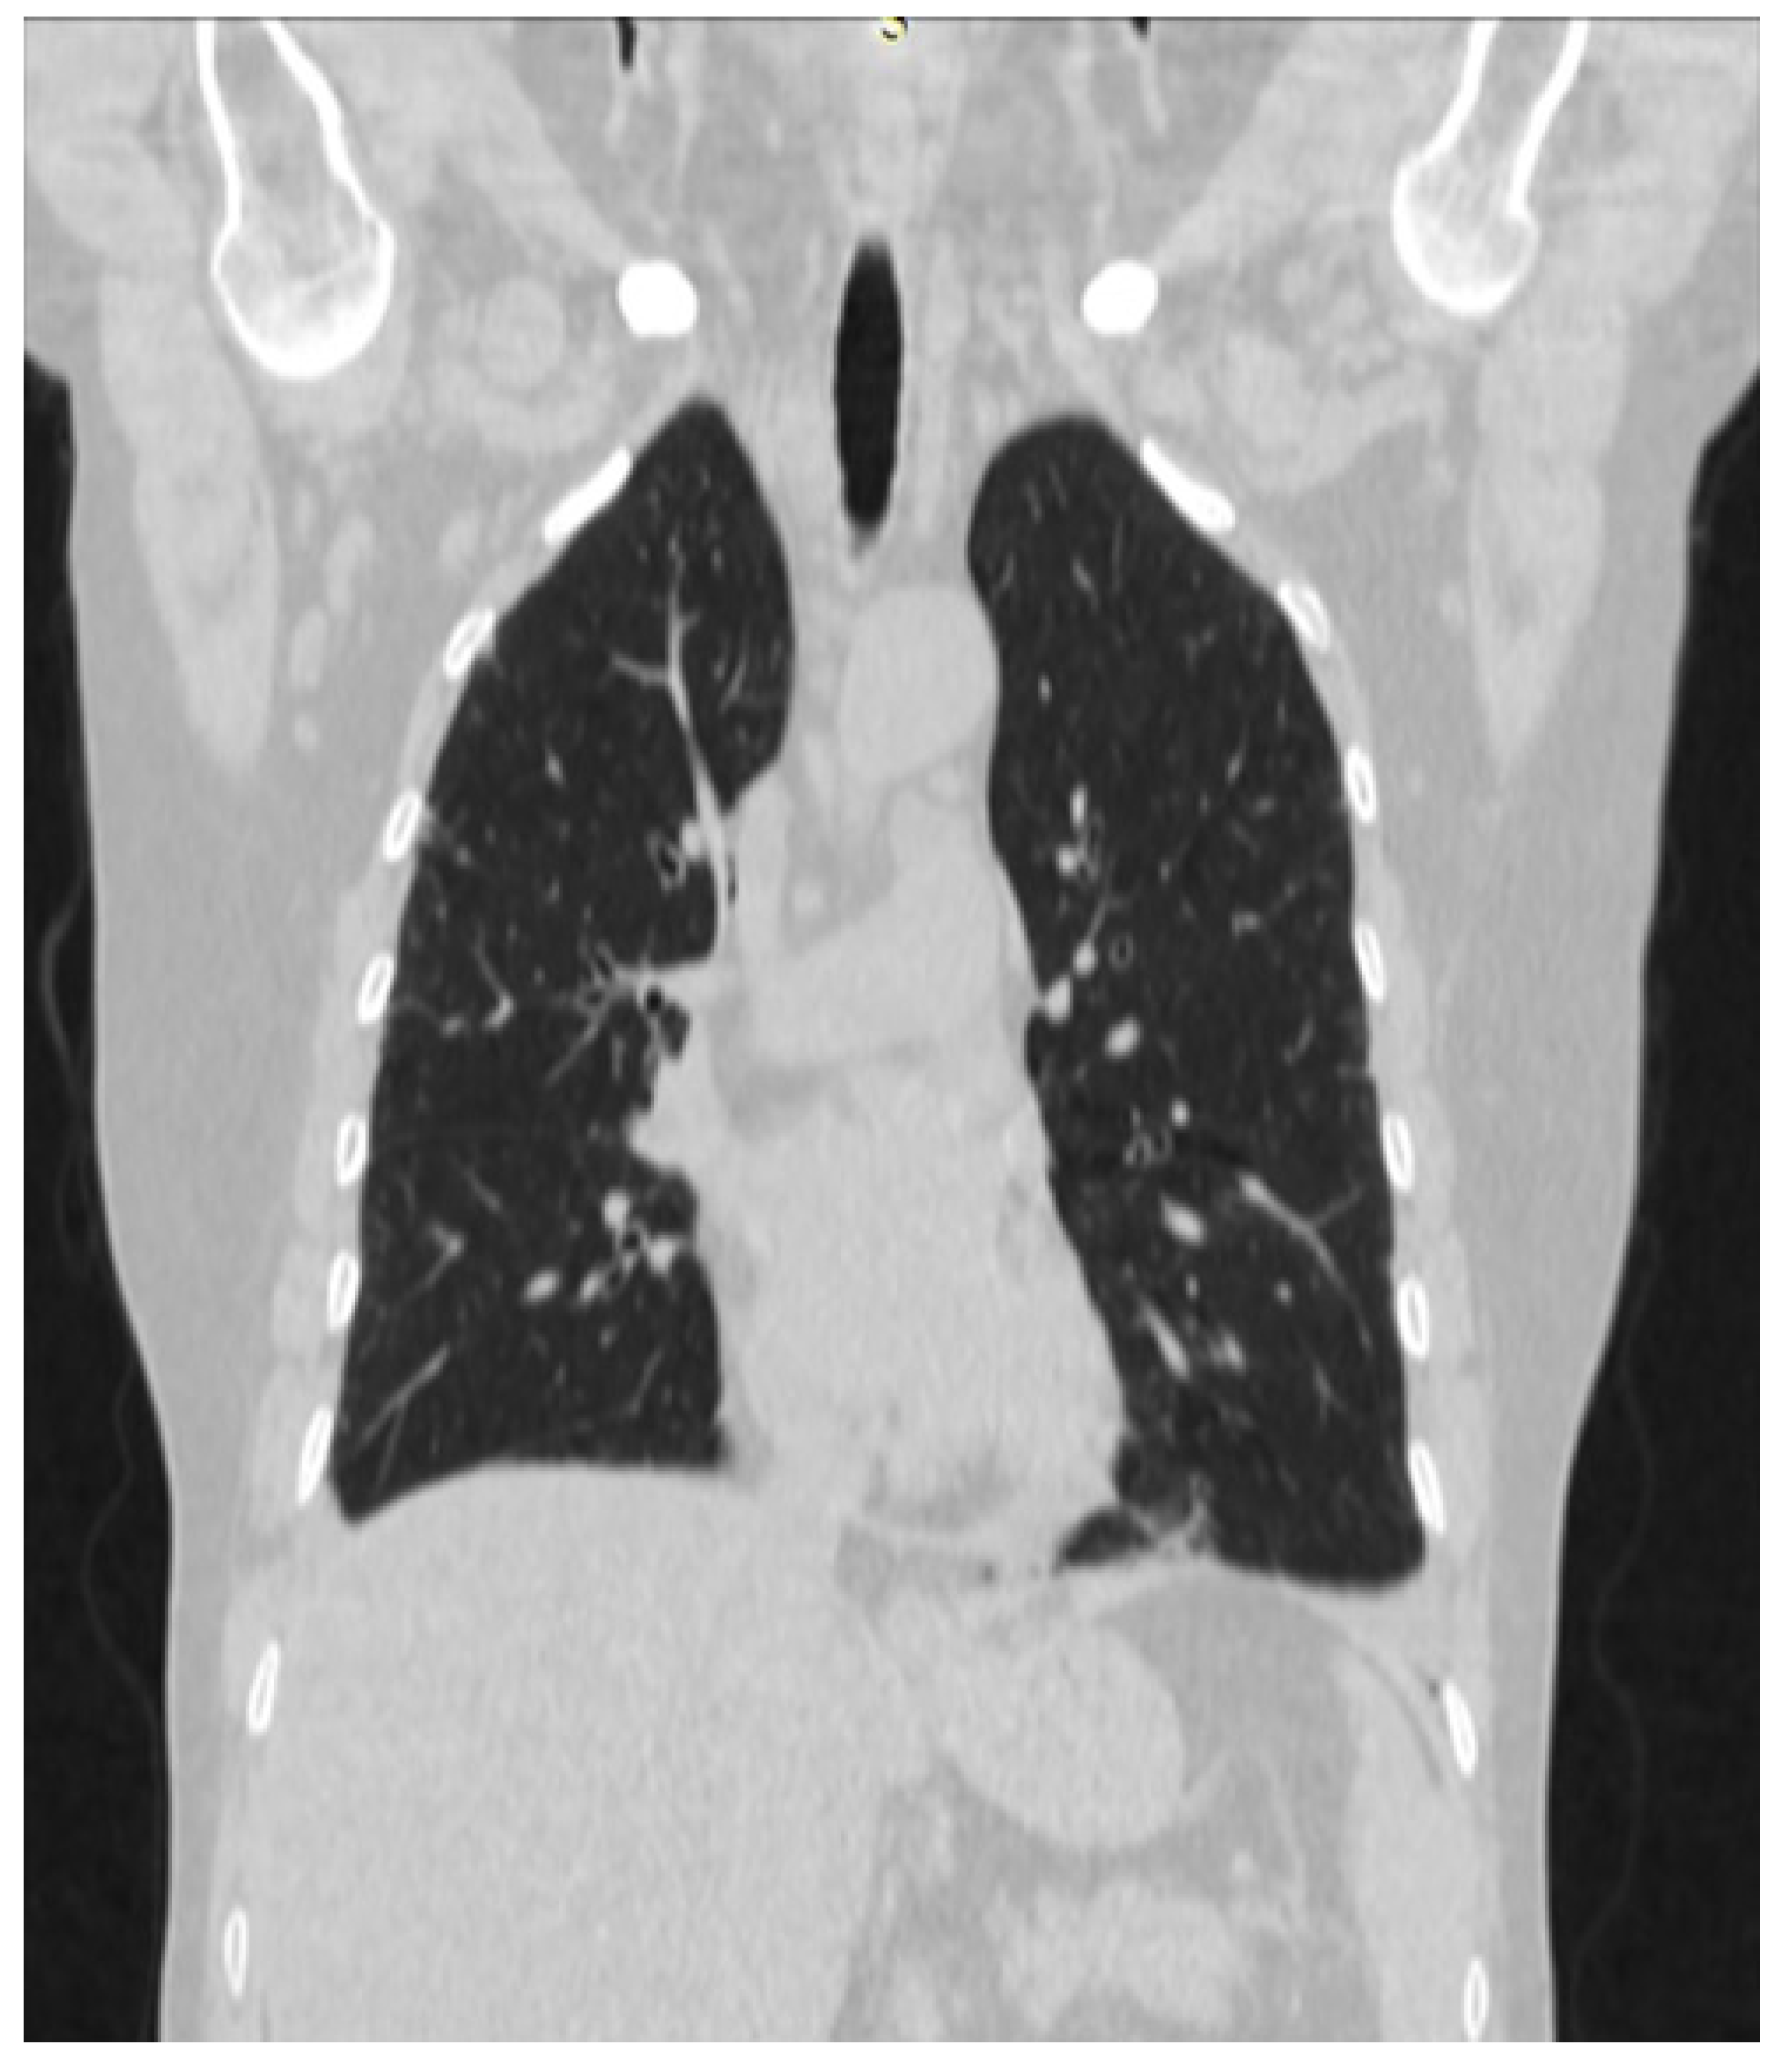

2. Case Presentation